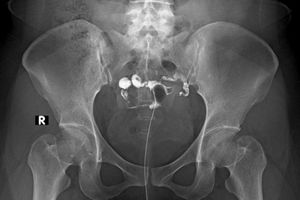

شکستگیها و دررفتگیها: اولین روش برای شناسایی شکستگیها و آسیبهای استخوانی است.

بررسی مفاصل: برای تشخیص آرتروز، عفونتها و بیماریهای مفصلی مانند التهاب مفاصل مفید است.